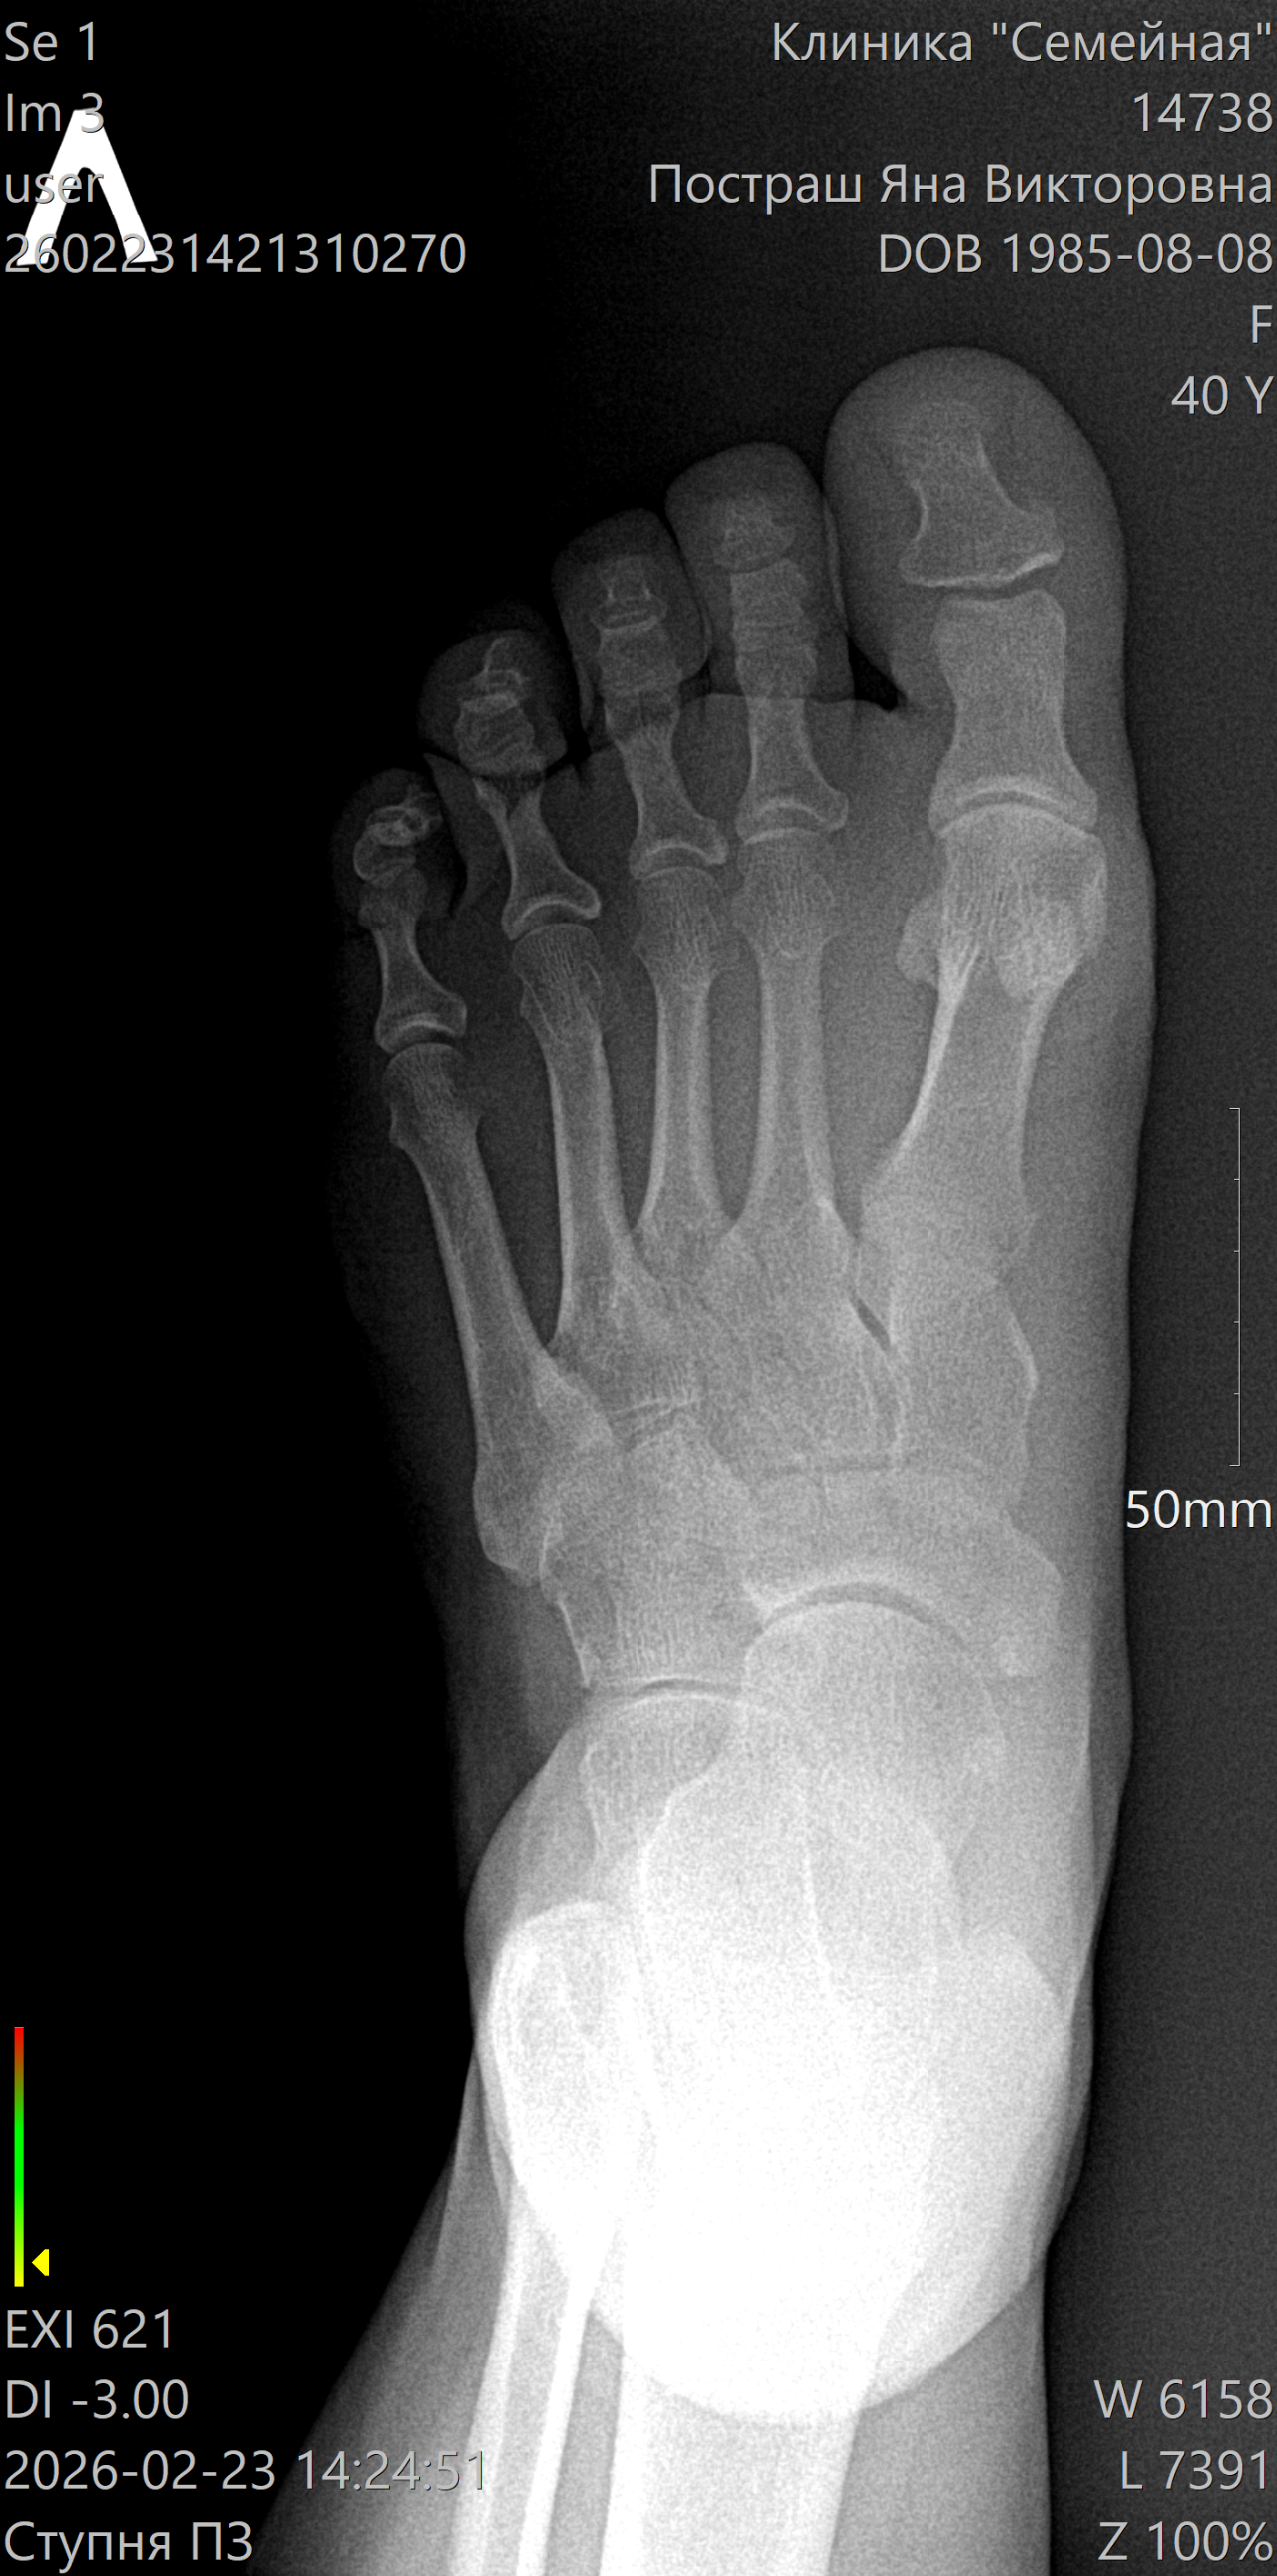

Краевой перелом дистальной фаланги

Несколько дней назад сильно ударила большой палец ноги. Поболело место ударно и все прошло бесследно. Спустя пару дней стала беспокоить боль в косточке при надавливании - сначала случайно задела, затем стала наблюдать. Боль не сильная, периодическая. Сделала рентген. К травматологу собираюсь на прием, но записи нет на ближайшее время. Внешне нога выглядит как обычно. Нет отека, синяка, подвижность не нарушена.

Какая моя тактика для заживления перелома?